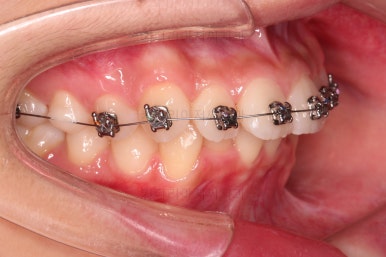

윗니가 가지런해진 뒤에는 부산치아교정치과 키다리아저씨치과에서는 ABP라고 하는 장치를 사용해 주면서 아랫니에도 브라켓을 부착합니다.

깊게 물리는 과개교합을 개선하기 위함인데요.

과개교합을 개선하기 위해서는 미니스크류를 사용하기도 하고 ABP를 사용하기도 하며, 윗니 앞니를 코 방향으로 밀어넣기도 합니다.

얼굴모습과 교합을 생각해서 각 케이스마다 모두 다른 방법을 적용해야 하므로 일관된 공식이 있는 것이 아닙니다.

이번 환자분은 ABP의 사용이 가장 적합했던 케이스였습니다.

ABP를 사용하지 않고도 과개교합이 매우 좋아졌고요.

위아래 치열이 매우 고르게 되었으며, 이제부터는 발치공간을 줄여나가면서 교합을 맞춰 나가면 됩니다.